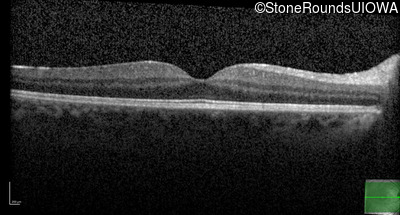

Optical Coherence Tomography - Right - 20/25

Exemplar / OCT Stack